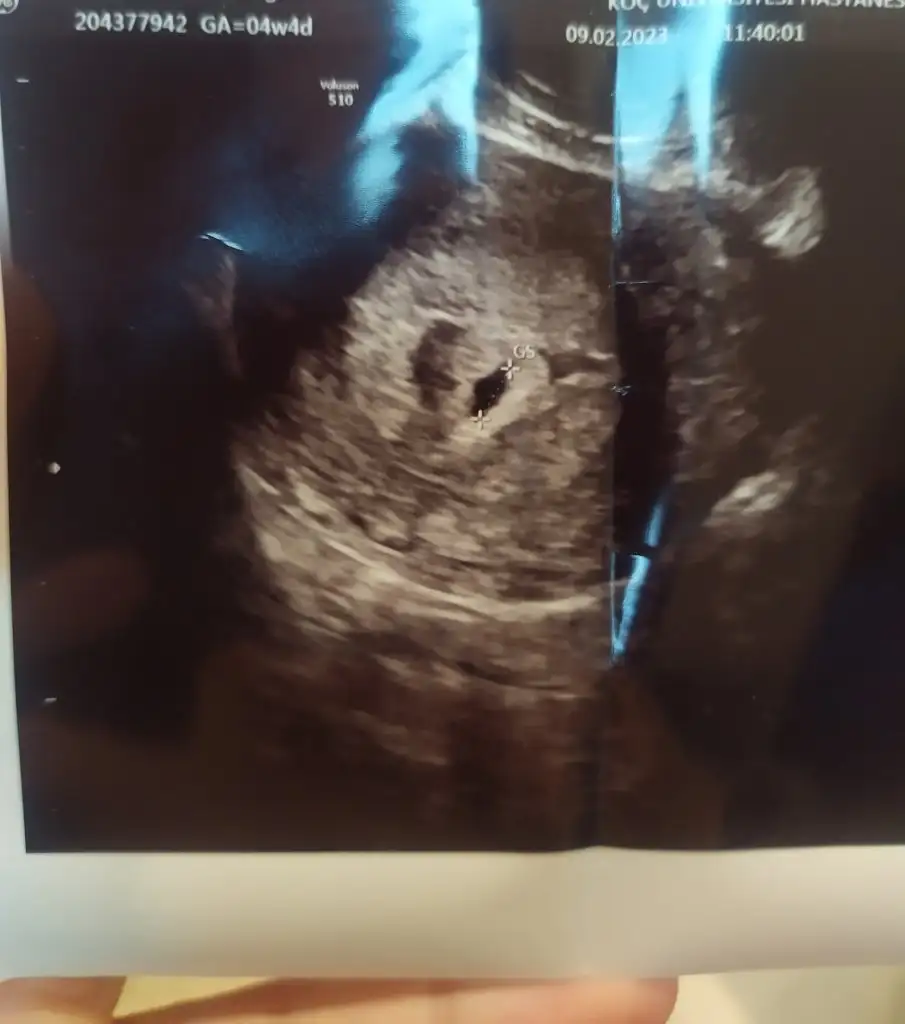

2 3 doktora gittim kesenin sekli degismis artik dedi doktor gelisme olmaz dedi 😔

Benimde dün kontrolüm vardı doktor kesemi. Düzensiz buldu..

Kese kanarinda kanama alanı var..

canımmm dün gittik, maalesef pek güzel haberler alamadım..

kesem hala duzensız ve saglıklık gebelık tanısı kondu..

kendı doktorum harıc rısklı gebelık doktorlarıda baktı görüşleri aynı..

maalesef ılacları kestık dusuk yapmayı beklıyorum..

olmaz ıse hap verdıler, oda olmaz ıse kurtaj dedı doktorum :(